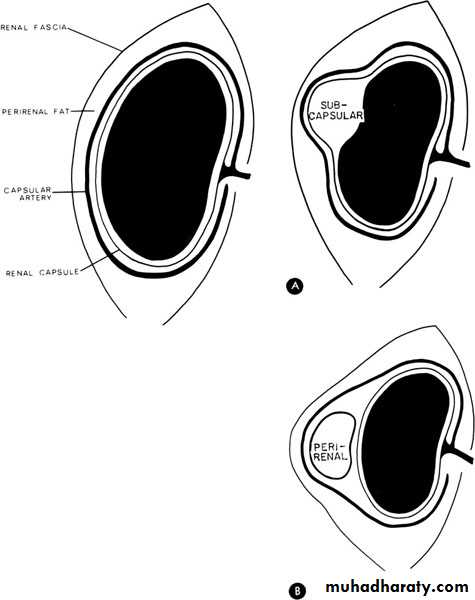

Perinephric abscess

Infection and pus collection in the perinephric space within Gerota’s fascia

U/S: pus collection around the kidney with or without hydronephrosis.

Drinage of perinephric abscess